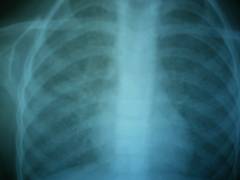

Обзорная рентгенограмма органов грудной полости. Диагноз: левосторонний экссудативный туберкулезный плеврит. Слева жидкость в плевральной полости на уровне 3-4 ребра. Справа – без особенностей.